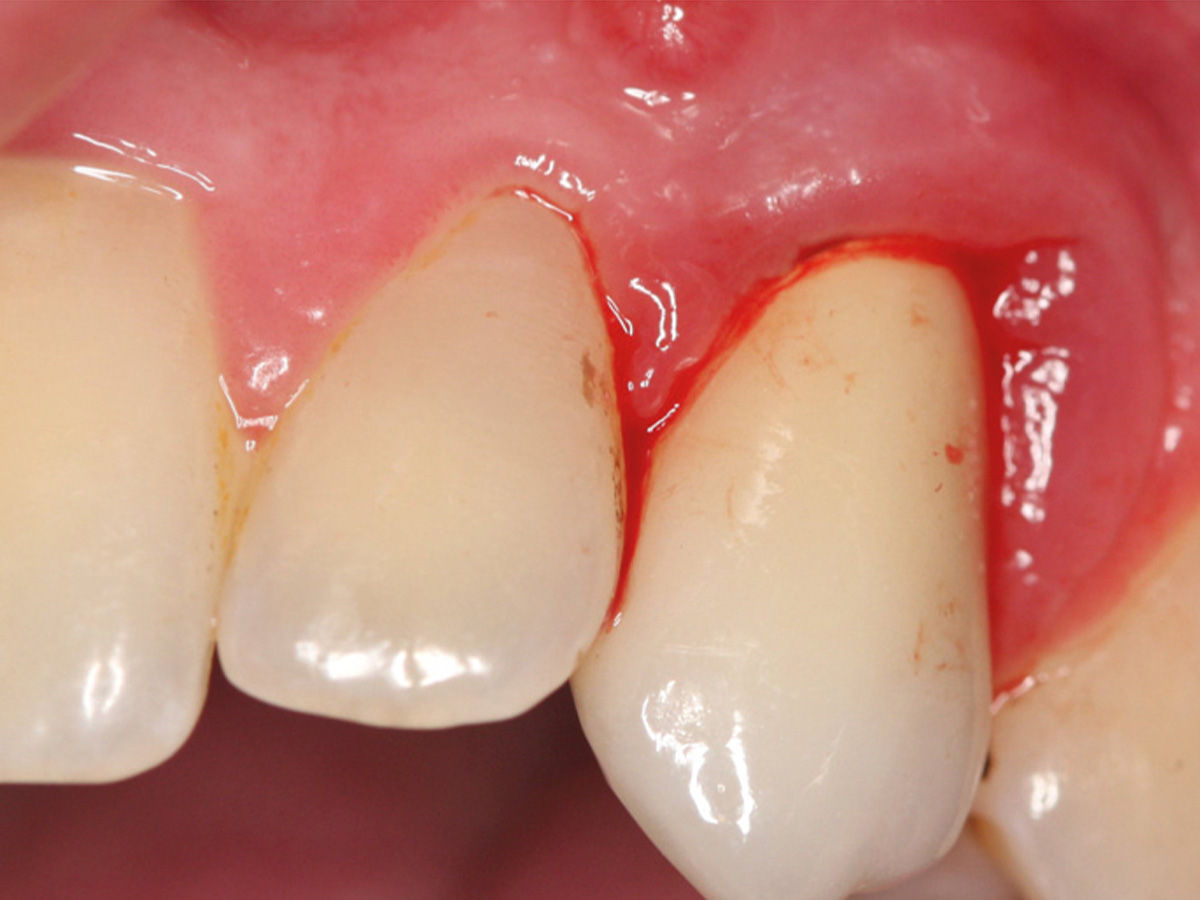

Abbildung 5

Provisorium.